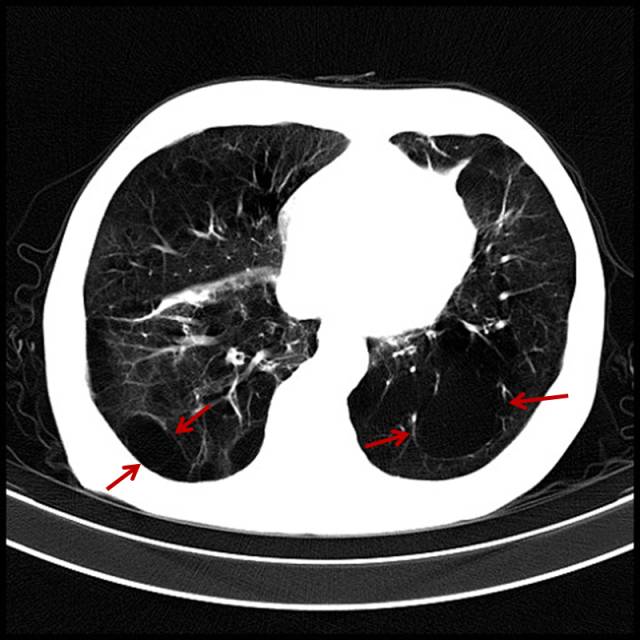

吸烟导致的中重度肺气肿

男,65岁,咳嗽、气短、吸烟几十年。

图片

图7

双肺多个小无肺纹区。有自觉症状,患者基本会意识到气短与吸烟有关。此类患者戒烟不戒烟,完全取决于自己的毅力。相当一部分患者已经成瘾,或者说成习惯了,会说慢慢戒、减量。我见过一天最多能吸5盒烟的。